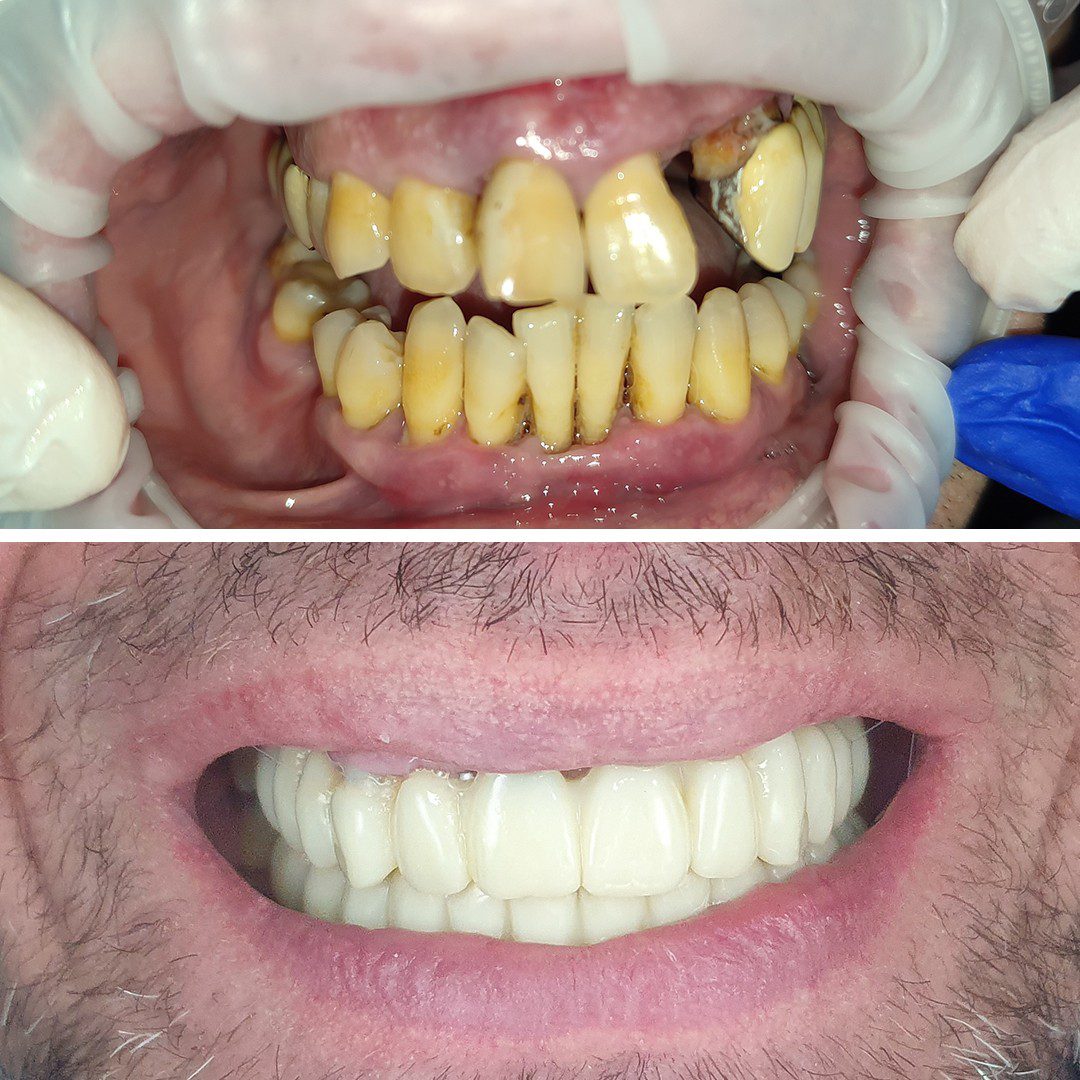

Dinți Ficși în 8-24 de ore pe implanturi dentare cu tehnica All-on-4/All-on-6 este cea mai eficientă și rapidă metodă de restaurare totală a danturii.

Este tratamentul ideal pentru pacienții care își doresc o dantură nouă, fixă și funcțională.

• Estetică deosebită, asemanatoare dinților naturali

• Stabilitate bună

• Funcționalitate